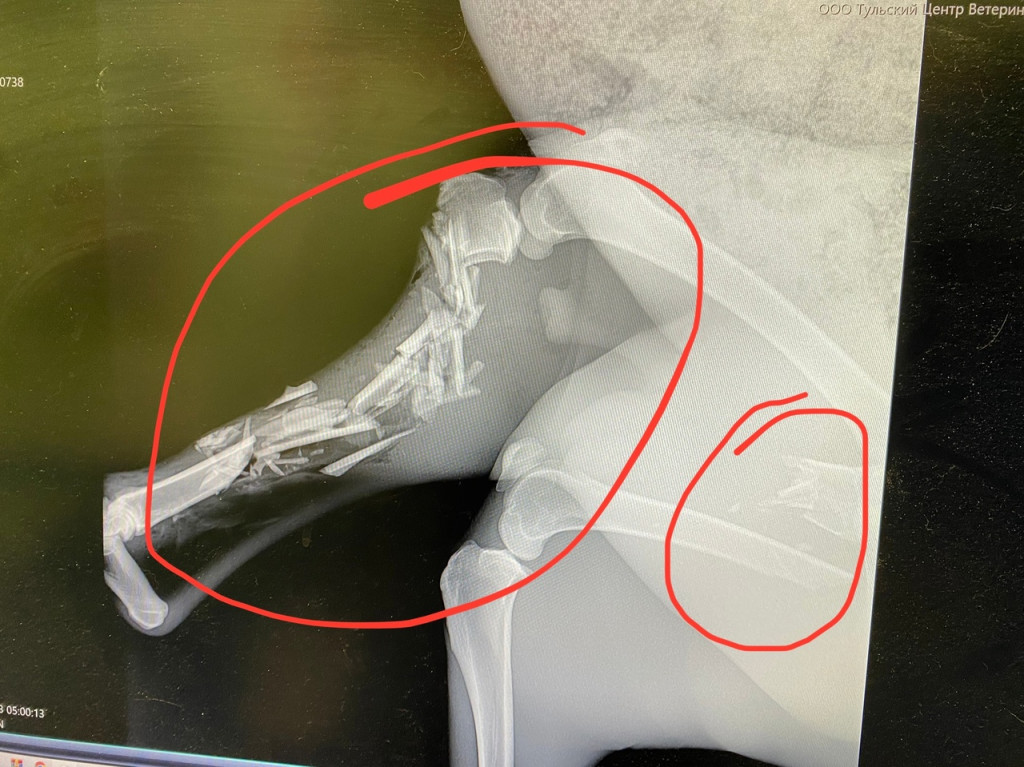

Рентген показал, что у животного сломаны лапы. Неравнодушные ветеринары согласили сделать косуле операцию. Самца доставят в Москву. Животному дали кличку — Мир.

Специалисты отмечают, что операция предстоит тяжелая, поскольку для косули даже небольшой перелом в большинстве случаев заканчивается гибелью.

До операции не дошло, обследование у хирурга в Москве показало проблемы, которых не было видно на тульском рентгене. Доктор объяснил негуманность операции.